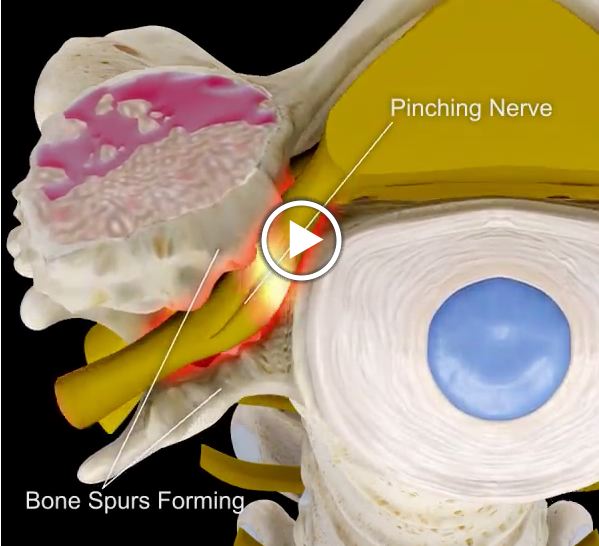

Disc In Neck: Bulging Disc In Neck With Bone Spurs

Thoracic Bone Spurs and Nerve Impingement – Request Physical Therapy

Arthritis (Spine) And Bone Spurs

Foraminal Stenosis of the Spine | Bone Spur | Dr. Donald Corenman …